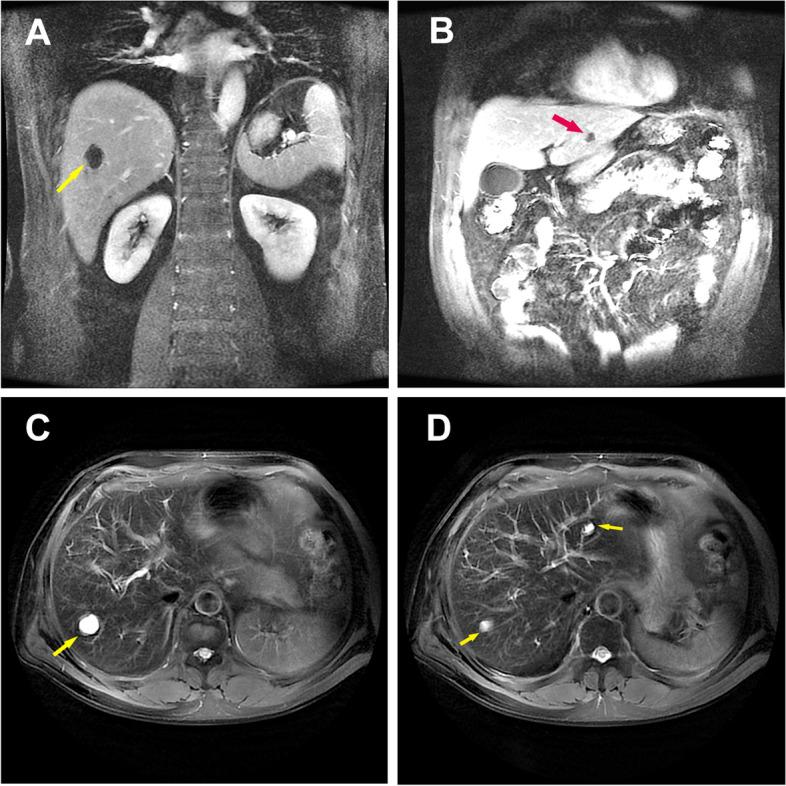

A 54-year-old male patient came to our department with a fever for 2 days and altered mental status for 1 day. Abdominal computed tomography (CT) and liver magnetic resonance imaging (MRI) revealed multiple liver abscesses. The blood culture was identified as Klebsiella pneumoniae sepsis. Head contrast-enhanced MRI and magnetic resonance venography (MRV) imaging showed multiple thrombus formation in the right transverse sinus and sigmoid sinus. The patient's infection and thrombosis were controlled within one week of multidisciplinary comprehensive treatment such as antibiotic and antithrombotic therapy, and a good clinical recovery during the 1-month follow-up.

一名 54 岁男性患者因发热 2 天伴精神状态改变 1 天来我院就诊。腹部 CT 和肝脏 MRI 显示多发肝脓肿。血培养鉴定为肺炎克雷伯菌败血症。头部增强 MRI 和磁共振静脉造影(MRV)成像显示右侧横窦和乙状窦多发血栓形成。经过多学科综合治疗(如抗生素和抗血栓治疗)一周后,患者的感染和血栓得到控制,在 1 个月的随访期间临床恢复良好。